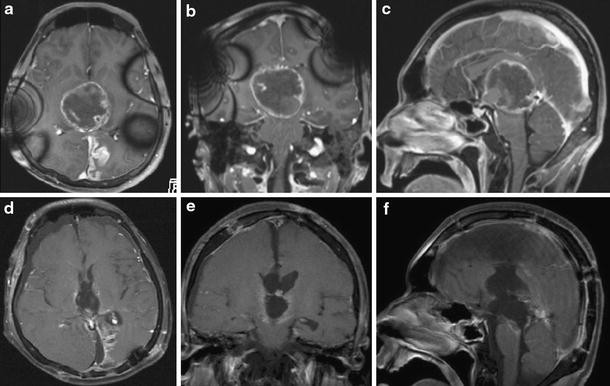

A 23-year-old man was transferred to our department because of progressive consciousness disturbance. He was drowsy on admission. A CT scan revealed a well-demarcated and heterogenous mass with calcification in the pineal region. The mass was approximately 40 mm in diameter, and extended into the lateral ventricles, causing obstructive hydrocephalus (Fig. 1). Based on the CT scan, a non-germinomatous germ cell tumor was suspected. The patient developed Cushing’s sign soon after admission. A neuroendoscopic biopsy was conducted for the lesion and ventriculoperitoneal (VP) shunting was performed. Endoscopic third ventriculostomy was not selected because the third ventricle was filled with the tumor. The lesion was reddish in color; histological diagnosis of the biopsy specimen was germinoma. Serum AFP concentration was 7.4 ng/ml (normal <10 mg/ml). HCG level was 4.6 mIU/ml (normal <1.0 mIU/ml), and HCG-β level was ≤0.1 ng/ml. In the cytological examination of cerebrospinal fluid, tumor cells were not detected. His consciousness disturbance persisted after the surgery. Although he subsequently underwent focal irradiation (20 Gy), the tumor enlarged. Two weeks after presentation, during irradiation, he developed deep venous thrombosis and pulmonary embolism. A filter was placed in the inferior vena cava and anticoagulant was administered. Systemic CT scan did not show abnormal mass lesions except for venous thrombosis. Three weeks after presentation, partial resection was carried out via an occipital interhemispheric transtentorial approach. Histological diagnosis was mature teratoma. The germinomatous component was not identified. Tumor enlargement during radiation was considered to be “the growing teratoma syndrome”. Whole-brain irradiation (24 Gy) was administered postoperatively. After tumor resection and irradiation, serum AFP concentration was to 2.4 ng/ml and HCG level was <1.0 mIU/ml. Three months after presentation, subtotal removal was carried out via an anterior transcallosal transchoroidal approach. The shunt system was also removed, because obstructive hydrocephalus improved. Histological diagnosis was mature teratoma without a germinomatous component. Serum AFP concentration was 1.5 ng/ml and HCG level was <1.0 mIU/ml after subtotal resection. In a series of cerebrospinal fluid examinations, tumor cells were not detected. The residual lesion was controlled (Fig. 2). His consciousness disturbance failed to improve, and he was bedridden.

Fig. 2

MR images taken during the course. ac MRI with contrast during radiation showing enlargement of the tumor, indicating growing teratoma syndrome. df MRI with contrast after the third surgery showing a residual lesion on the right side of the third ventricle